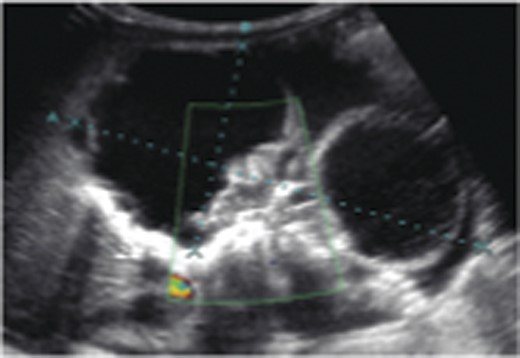

The case was referred to the Pediatric Surgery team postnatally. Birthweight was 3.6 kg. Apart from a distended abdomen, the child appeared grossly normal. Abdominal radiograph showed curvilinear calcifications over the right abdomen (Fig. 1). Ultrasonography (USG) revealed the presence of an echogenic line resembling long bones, giving rise to a provisional diagnosis of FIF (Fig. 2). An alpha feto protein (αfp) level taken at birth was markedly elevated at 13 200 IU/ml. Normal range of αfp at our center is taken to be 0–5.8 IU/ml at birth.

Diagnosis is most often by imaging. Both magnetic resonance imaging and USG lack ionizing radiation and are ideal imaging modalities. Due to its wide availability, low cost and real-time imaging, USG has become the investigation of choice for diagnosis of fetal structures and various growth anomalies. It is the imaging modality of choice at our center.